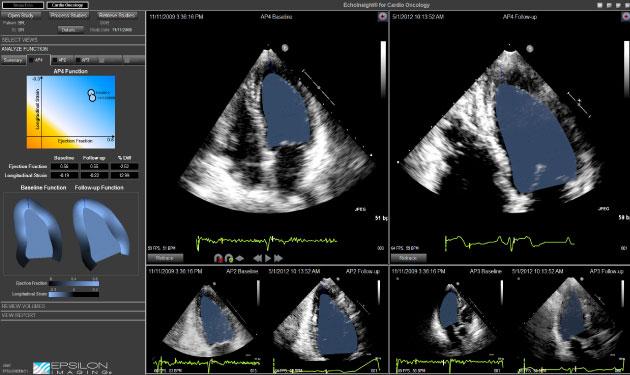

Based on the ASE guidelines, the suite includes automated linear, area and volumetric measurements designed to save time and improve standardization in echo analysis. Developed specifically for the clinical environment, EchoInsight is vendor-neutral and now includes an automated measurement suite, practical application-specific strain imaging, and rapid study comparison and trending for comprehensive assessment and patient monitoring in echo.

- "The Use of Two-Dimensional Speckle-Tracking Strain in Monitoring Cardiotoxicity in Older Patients with Acute Myeloid Leukemia (AML)," presented by Nausheen Akhter, et al. from Northwestern Memorial Hospital. The study analyzed 25 AML patients enrolled in the ECOG2906 study (standard cytarabine and daunorubicin vs. clofarabine [Genzyme/Sanofi]). Echo studies were performed before and after induction of therapy. 2-D speckle-tracking echo was performed using EchoInsight. The study concluded four-chamber longitudinal strain can be used to follow cardiotoxicity in patients undergoing induction 7+3 chemotherapy. Patients treated with 7+3 were noted to have both subclinical and clinically significant changes in left ventricular (LV) function. These changes were not seen in the clofarabine group. These findings suggest that changes in LV function occur shortly after exposure to relatively low doses of anthracycline in older patients with AML.